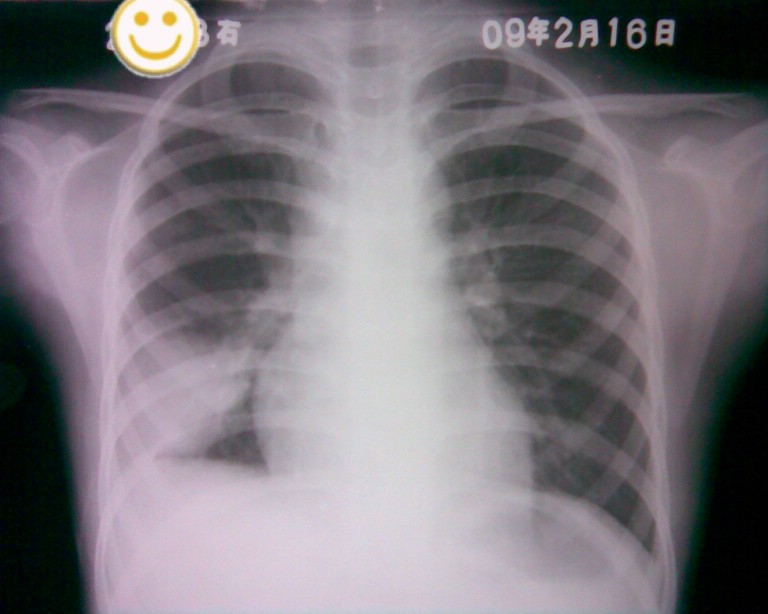

标题: PED1836:女,9岁,发热5天,听诊两肺呼吸音粗 [打印本页]

标题: PED1836:女,9岁,发热5天,听诊两肺呼吸音粗

节段性肺炎。典型!

节段性肺炎。典型!!!

节段性肺炎。片资料完整。

应该是胸膜炎